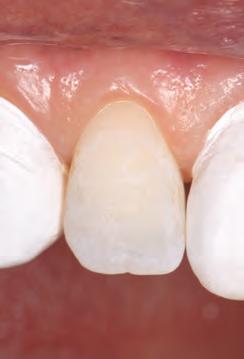

A 31-year-old woman presented with cosmetic concerns regarding her smile and requested a conservative enhancement. After clinical and radiographic analysis, digital 35mm photographs were taken and reviewed by the restorative clinician, technician, and surgeon (Fig 1). A digital impression was taken of the maxillary and mandibular arches using an intraoral scanner (Trios 3, 3Shape; Fig 2), and a smile design was developed with NemoSmile Design 3D software (Nemotec; Fig 3a). This allows for a facially driven smile frame to be created using reference lines of facial and smile proportions and natural teeth shapes and textures from the digital library (Fig 3b).

After developing the simulated mock-up, a 3D-printed resin model was created using CAD software (Fig 4a), and a clear PVS matrix (Exaclear, GC America) was fabricated to replicate the printed diagnostic wax-up using a nonperforated tray (Fig

Fig 1 Preoperative clinical views of a 31-year-old woman presenting with diastemas and limited tooth visibility. (top) Portrait. (center row) Intraoral views. (bottom row) Smile.

4b). This matrix was used to create an intraoral motivational mock-up with bis-acryl composite (Luxatemp Ultra, DMG). This additive mock-up provides the interdisciplinary team with an intraoral translation for evaluation (Fig 5). Upon evaluation of the digital smile frame and the clinical translation, it was determined that multiple esthetic and restorative requirements were necessary for an optimal biologic framework, and the interdisciplinary team determined the best sequence for these procedures. The patient was presented with the interdisciplinary treatment possibilities that included restoring the maxillary anterior teeth and premolars with a minimally

invasive preparationless procedure or with less conservative veneer preparations. The restorative materials discussed included injectable resin composites and ceramic (ie, feldspathic, pressable, machinable). For an optimal biologic framework and health, it was determined that connective tissue grafting would be necessary for treatment of the recessiontype defects on the maxillary left central and lateral incisors, canine, and premolars. The patient opted for the conservative preparationless composite veneers using the injectable resin technique followed by a connective tissue surgical procedure using the tunneling technique.